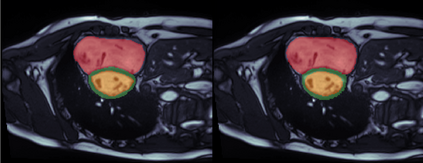

Supervised machine learning provides state-of-the-art solutions to a wide range of computer vision problems. However, the need for copious labelled training data limits the capabilities of these algorithms in scenarios where such input is scarce or expensive. Self-supervised learning offers a way to lower the need for manually annotated data by pretraining models for a specific domain on unlabelled data. In this approach, labelled data are solely required to fine-tune models for downstream tasks. Medical image segmentation is a field where labelling data requires expert knowledge and collecting large labelled datasets is challenging; therefore, self-supervised learning algorithms promise substantial improvements in this field. Despite this, self-supervised learning algorithms are used rarely to pretrain medical image segmentation networks. In this paper, we elaborate and analyse the effectiveness of supervised and self-supervised pretraining approaches on downstream medical image segmentation, focusing on convergence and data efficiency. We find that self-supervised pretraining on natural images and target-domain-specific images leads to the fastest and most stable downstream convergence. In our experiments on the ACDC cardiac segmentation dataset, this pretraining approach achieves 4-5 times faster fine-tuning convergence compared to an ImageNet pretrained model. We also show that this approach requires less than five epochs of pretraining on domain-specific data to achieve such improvement in the downstream convergence time. Finally, we find that, in low-data scenarios, supervised ImageNet pretraining achieves the best accuracy, requiring less than 100 annotated samples to realise close to minimal error.